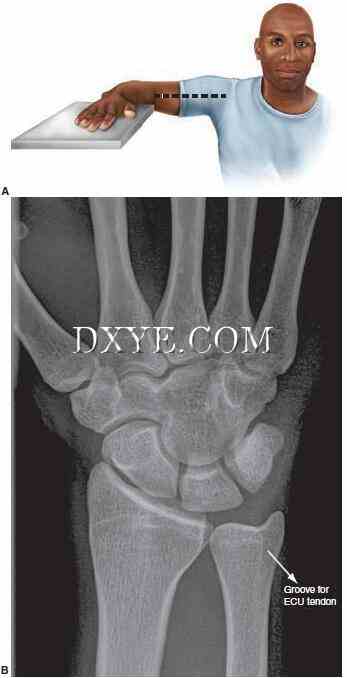

前后位(PA)和侧位片是常规的。 PA视图是在90°外展的肩部,90°屈曲的肘关节以及中立旋转的手腕和前臂的情况下获得的(图76.3A)。 在一个真正的PA标准视图中,尺侧腕伸肌腱的沟槽应位于尺骨茎突基部的水平或径向(图76.3B)。 肩关节90°内收,肘关节屈曲90°,手与肱骨相同(图76.4A)。 在真正的侧面图中,豌豆皮的掌侧皮层应覆盖远侧舟骨掌侧皮质和头状体头部之间的中间三分之一(图76.4B)。

图 76.3.  手腕的标准PA射线照片。 A. 定位手腕PA射线照片。 B. 正确定位的PA视图显示了尺骨茎突桡骨的ECU凹槽。